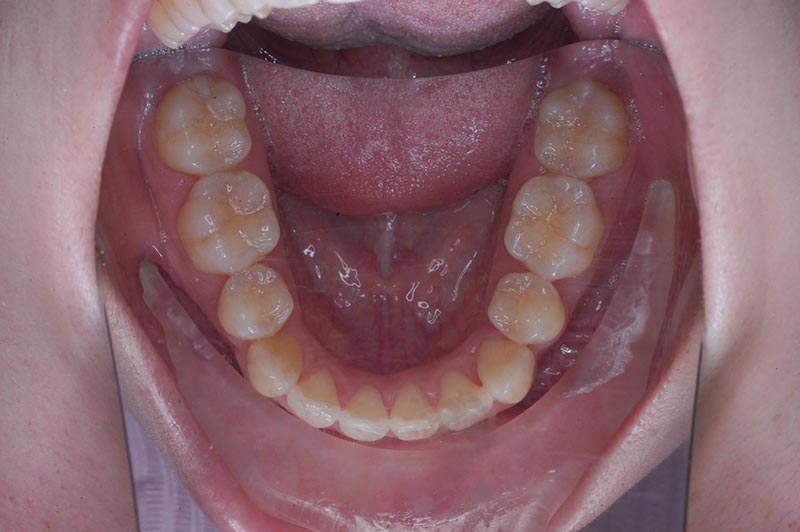

主訴 口が閉じづらい 診断名 アングルⅠ級上下顎前突症例

初診時年齢 19歳5ヵ月 性別 動的治療期間 26ヵ月

口腔内所見 大臼歯関係はⅠ級。顔面正中に対して上顎正中は一致しており、下顎正中は右側に偏位していた。上下顎前歯は大きく唇側傾斜し、overjetが7.8mmの上突咬合、両突歯列、叢生歯列弓であった。

批評・予后 上顎大臼歯のアンカーロスも生じず、大幅な前歯舌側移動、咬合の緊密化、歯根のパラレリングは行えた。上下口唇形態は改善し、良好なプロファイルが得られた。